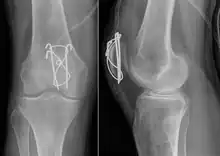

Most patella fractures are transverse or comminuted, hence the quadriceps mechanism is disrupted and they are treated by a combination of wires in a tension band construct. This unites the fractured bones, reconstructing the straightening mechanism of the leg.[5][6]

Comminuted fracture of patella